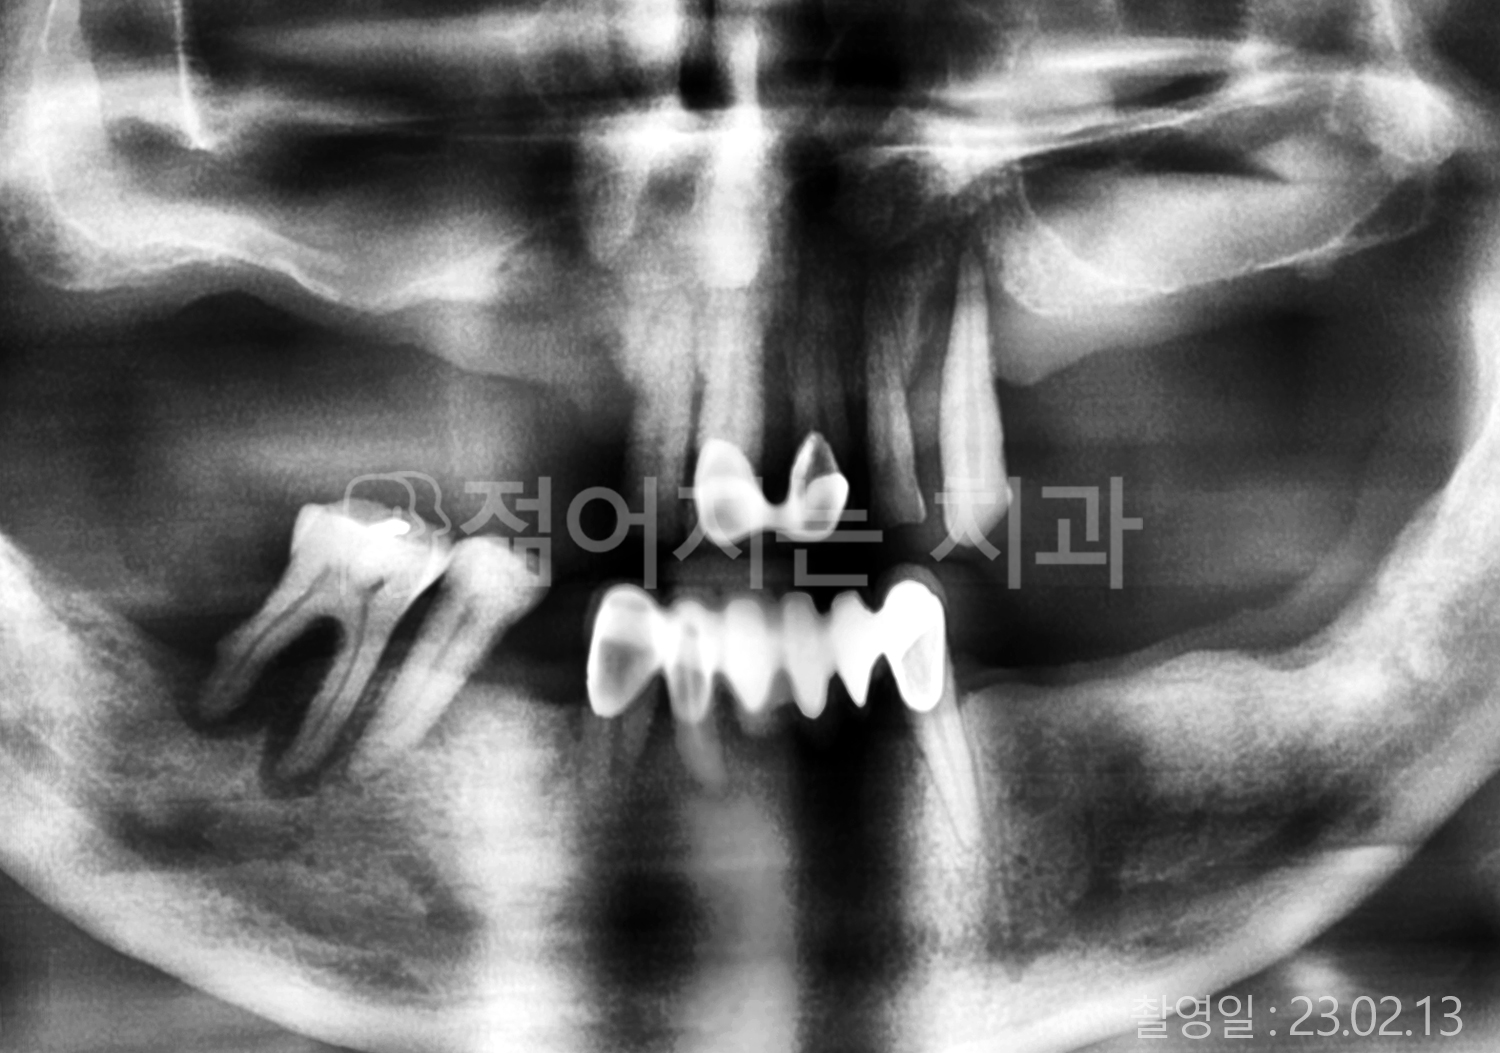

• 50대 고혈압, 당뇨, 고지혈증 전체치아 10개 이상 임플란트

• 60대 골다골증, 간경화 전체치아 10개 이상 임플란트

• 60대 고혈압, 고지혈증 전체치아 10개 이상 임플란트

• 50대 고혈압, 당뇨 전체치아 10개 이상 임플란트

• 60대 고혈압 전체치아 10개 이상 임플란트

• 60대 전체치아 10개 이상 임플란트

• 60대 고지혈증 전체치아 10개 이상 임플란트

• 40대 전체치아 10개 이상 임플란트

• 70대 전체치아 10개 이상 임플란트